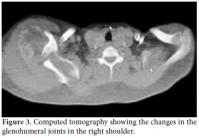

Radiological examinations showed destruction in the joints and bone structure of the affected right shoulder, elbow, and wrist as well as soft tissue calcification (Figure 2). Upper extremity computed tomography (CT) also indicated that the bilateral glenohumeral joint relations were disturbed. The joint on the right was dislocated, and both humeral heads were destructed and fragmented, with the damage more visible on the right side. Furthermore, extensive soft tissue calcification was noted in the neighborhood of the joints together with destructive changes in the glenoid fossa and proximal humeral metaphysis. Additionally, the lesions that showed bilaterally similar but moderately asymmetric involvement were evaluated with regard to neuropathic arthropathy (Figure 3).